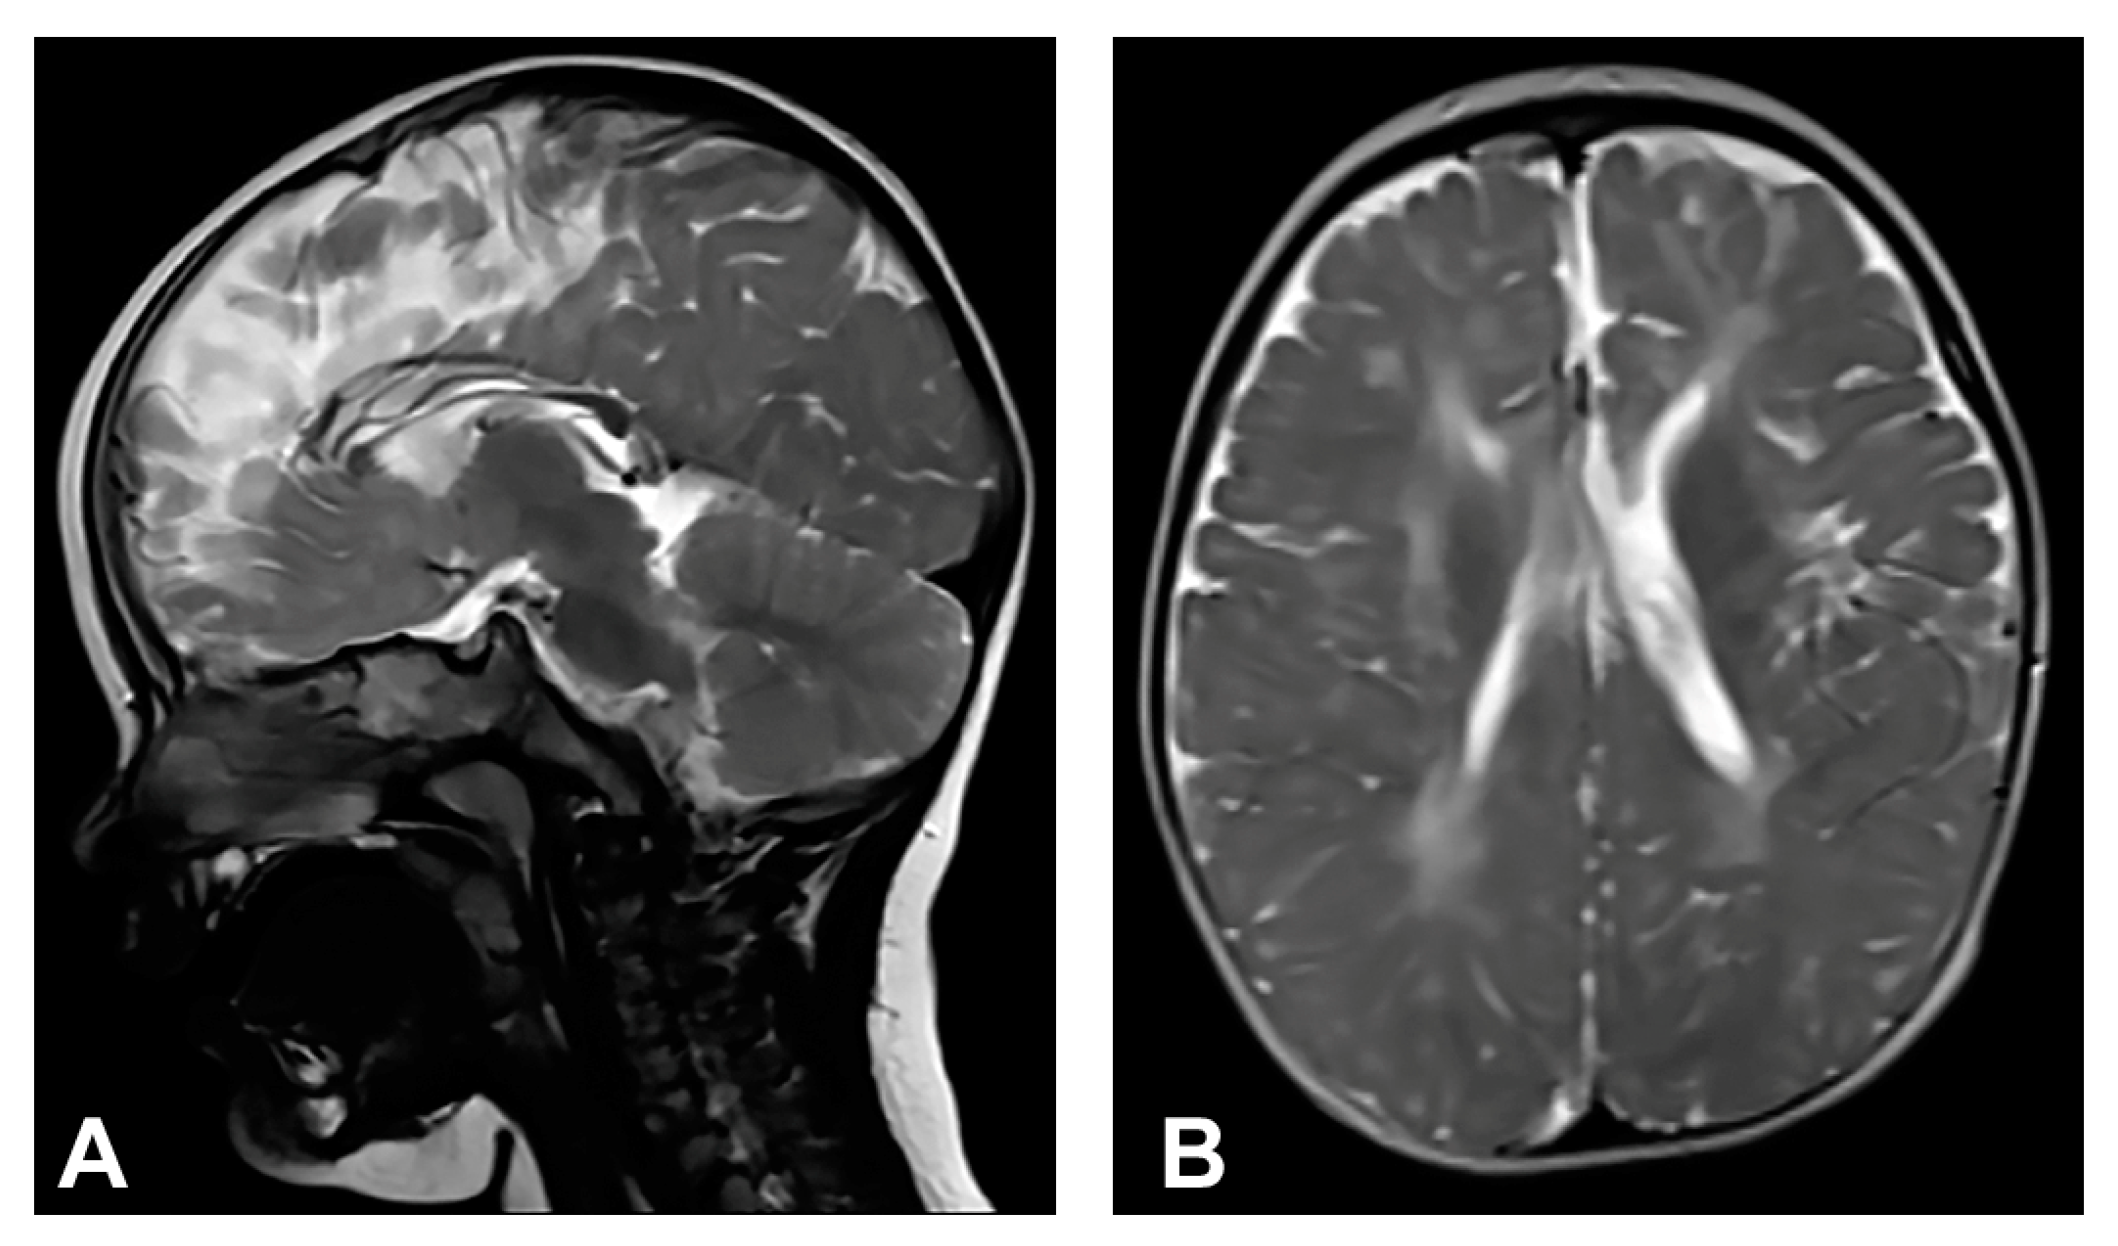

The patient started to walk unsupported from the age of two and a half with both feet in valgus position. Upon teeth eruption, the patient presented peg-like teeth. At the age of five, she had spastic quadriparesis with paraparetic gait, prominent speech delay and moderate intellectual disability. MRI of the brain showed macrocrania with bilateral loss of white matter volume in the frontal regions, dilated extracerebral liquor spaces and slightly dilated lateral ventricles (Figure 1). White matter abnormalities (gliosis) in periventricular and frontal regions were observed, as well as, hypoplasia of CC with slightly thinner body and a pineal gland cyst.

Figure 1.

(Case 1) (A) Sagittal T1 MPRAGE magnetic resonance image at the age of two shows macrocrania, thinning of CC and a pineal gland cyst. (B) Coronal T2W magnetic resonance plane shows mild atrophy of bilateral frontal white matter with dilated extracerebral liquor spaces. (C,D) Axial T2 FLAIR magnetic resonance planes show that lateral ventricles are slightly dilated with gliotic changes in periventricular and frontal regions.